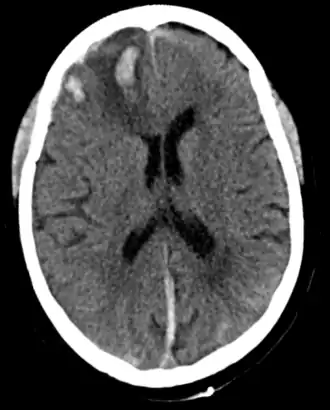

In de rechter frontale kwab (linksboven op de afbeelding) wordt een bloedingshaard gezien, passend bij hersenkneuzing

Een hersenkneuzing[1] of contusio cerebri[1] is een vorm van traumatisch hersenletsel en is, zoals het woord al zegt, een kneuzing van de hersenen. Bij een hersenkneuzing treedt per definitie bewusteloosheid op (maximaal 30 minuten), vaak geheugenverlies (maximaal 24 uur) en soms neurologische uitvalsverschijnselen. Op beeldvormend onderzoek van de hersenen (bijvoorbeeld een MRI-scan of een CT-scan) worden een of meerdere bloedingshaarden (kneuzingen) in de hersenen gezien.